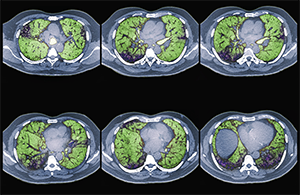

Colored CT scans of axial sections through the chest of a 68-year-old patient with ILD.

Zephyr/ScienceSource.com